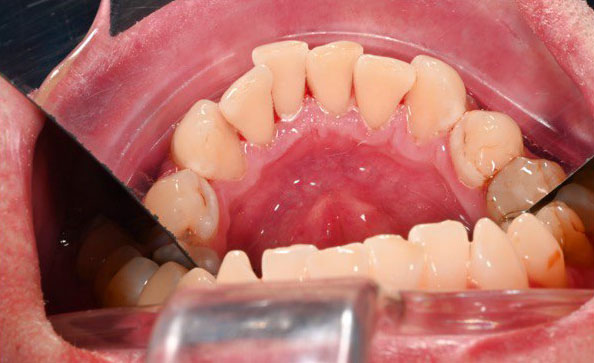

В ходе первичного осмотра выявлено значительное количество пигментированного налета и твердых зубных отложений, особенно в пришеечной области и на внутренней поверхности зубов. Также отмечались признаки воспаления десен, характерные для начальных проявлений гингивита. Пациенту были даны рекомендации по проведению комплексной профессиональной гигиены полости рта.

Пациенту проведена комплексная профессиональная гигиена полости рта. На первом этапе выполнено удаление твердых зубных отложений. Далее с использованием аппарата AirFlow произведено удаление пигментированного налета и мягких отложений с поверхности зубов. Завершающим этапом стала полировка эмали, направленная на создание гладкой поверхности и замедление повторного накопления налета.